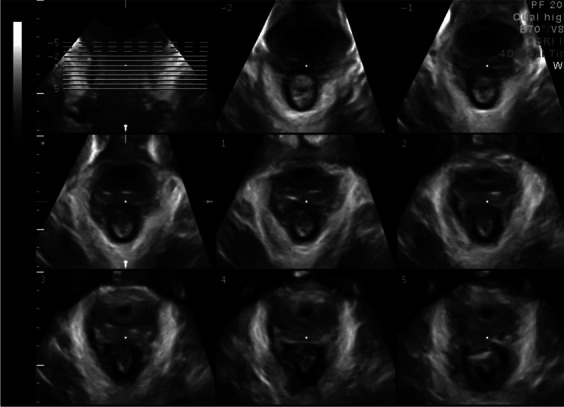

Endoanal ultrasound (EAUS) or anal endosonography (AES)

Ultrasound of the anal canal performed with a pole-like ultrasound probe placed in the anal canal giving a 360 degree image of the anal canal (Figure). It is usually performed with the patient placed in the lithotomy, prone position or sometime left lateral. Two dimensional AES; three dimensional AES—three-dimensional reconstruction of the anal canal is performed using either axial or sagittal images [7] (Fig. 5). FN3.4

Fig. 5.

Endoanal ultrasound images showing normal appearance of the internal (IAS) and external (EAS) anal sphincters [47].

Source: Reprinted by permission from Springer Nature